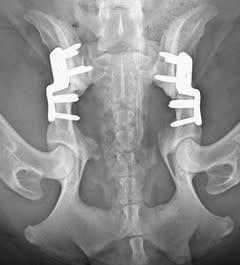

Bekkenkanteling (TPO)

Bij een bekkenkanteling wordt de heupkom van je kat in de juiste positie vastgezet. Hiervoor wordt het bot op 3 plaatsen doorgezaagd om zo het bekken te kunnen kantelen, waardoor het dijbeen weer terug mooi in de heupkom gepositioneerd wordt. Na 6 tot 10 weken is de heup van je kat weer in de juiste positie vastgegroeid. Beide heupen kunnen apart of in een keer behandeld worden.

Deze operatie is geschikt voor katen die bij voorkeur jonger zijn dan 12 maanden. Oudere katen hebben door artrose meestal geen baat meer bij deze operatie. Vraag steeds raad aan een AniCura-dierenarts.

Bekkenkanteling (DPO)

DPO is vergelijkbaar met TPO alleen blijft het zitbeen bij deze operatie intact. De ingreep is minder pijnlijk en je kat herstelt sneller dan bij TPO. Beide heupen kunnen in een keer geopereerd worden. DPO is alleen mogelijk wanneer de bekkenbodem van je kat voldoende flexibel is.